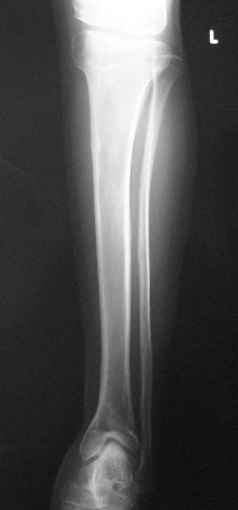

Доброго времени времени суток коллеги. Хотелось бы услышать Ваше мнение по поводу тактики лечения данного пациента 14 лет. Перенес эпифизарный остеомиелит, чего теперь установить сложно. Перенес множество операций в нашей стране.Корригирующие остеотомии бедра голени. Удлинение 2 раза бедро 2 раза голень. В настоящий момент укорочение нижней конечности 7 см - 5 голень 2 бедро. Разгибательная контрактура коленного сгибание до 90. Эквинус стопы до 110. Вальгус г/с сустава, но его стопа не беспокоит совсем только желание удлинение сегмента. Стоит ли трогать голеностопный сустава и только удлинить голень с устранением эквинуса.